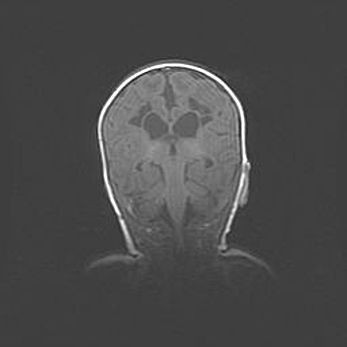

Открытая гидроцефалия.

Возраст: 9 месяцев 12 дней

Вес: 6800 г

Пол: мужской

Окружность головы: 41,5 см

Срок гестации: 28 недель

Гидроцефалия головного мозга у новорожденных имеет характерный признак: опережающий рост окружности головы приводит к визуально хорошо определяемой гидроцефальной форме сильно увеличенного в объёме черепа. Детские неврологи определяют следующие симптомы гидроцефалии у грудничков: выбухающий напряжённый родничок, частое запрокидывание головы, смещение глазных яблок к низу.